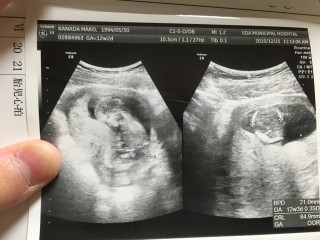

今回から腹部エコーになりました。かなり分かりにくいですが、左が頭で右が体です。 背骨や足の骨も確認でき、背中のうしろもキレイだと言われてホッとしました。 お尻や手を動かして元気に動いてくれていました♪(*^▽^)v 頭の大きさ:2.3cm

頭からお尻までの大きさが6㎝で、頭が2㎝でした。 お顔も見せてもらいました。 小さな手が動いているのがとっても可愛らしかったです。